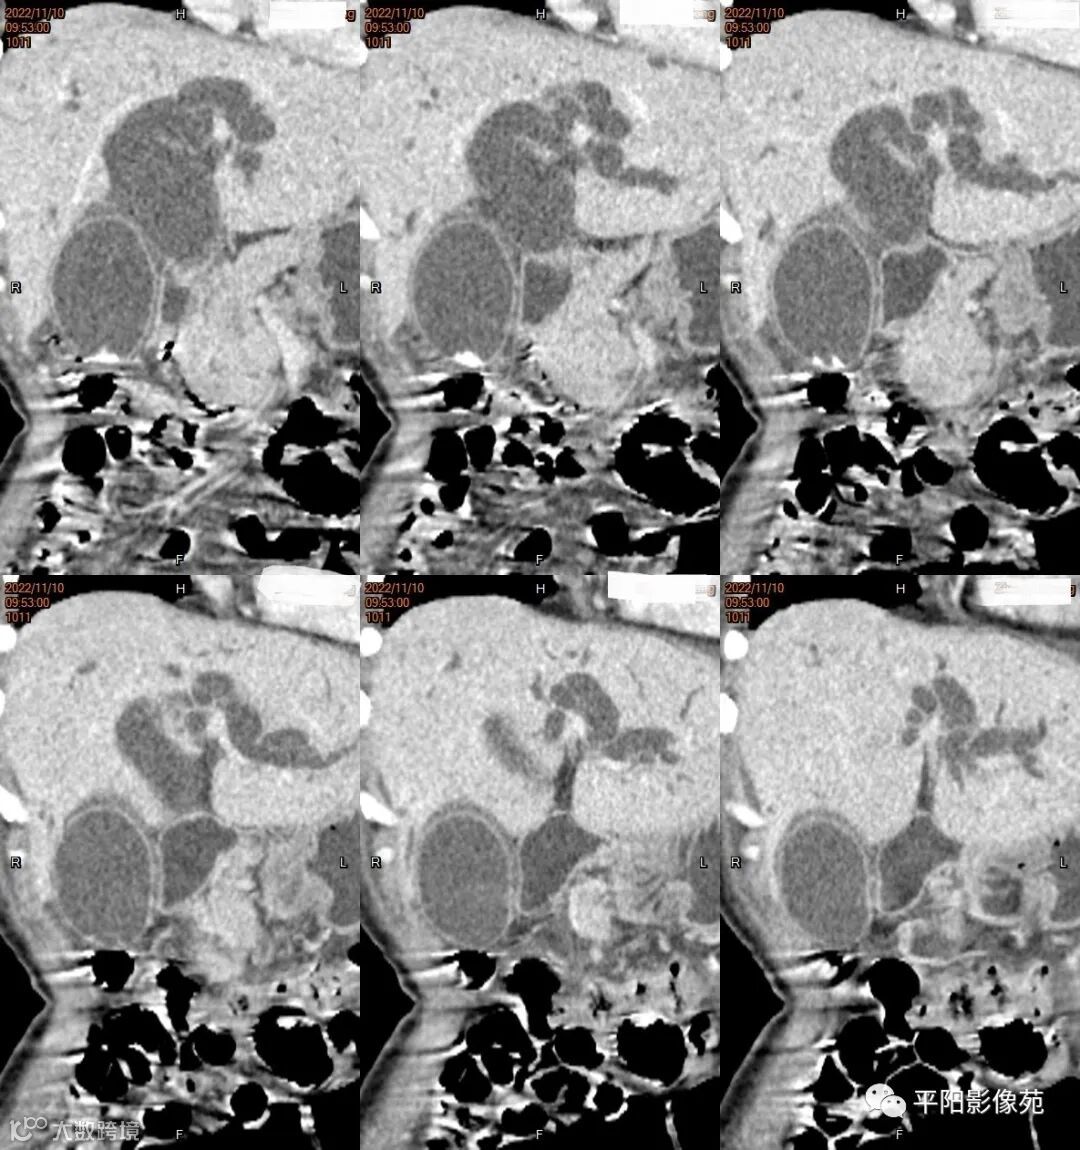

影像学检查

CT

影像表现: